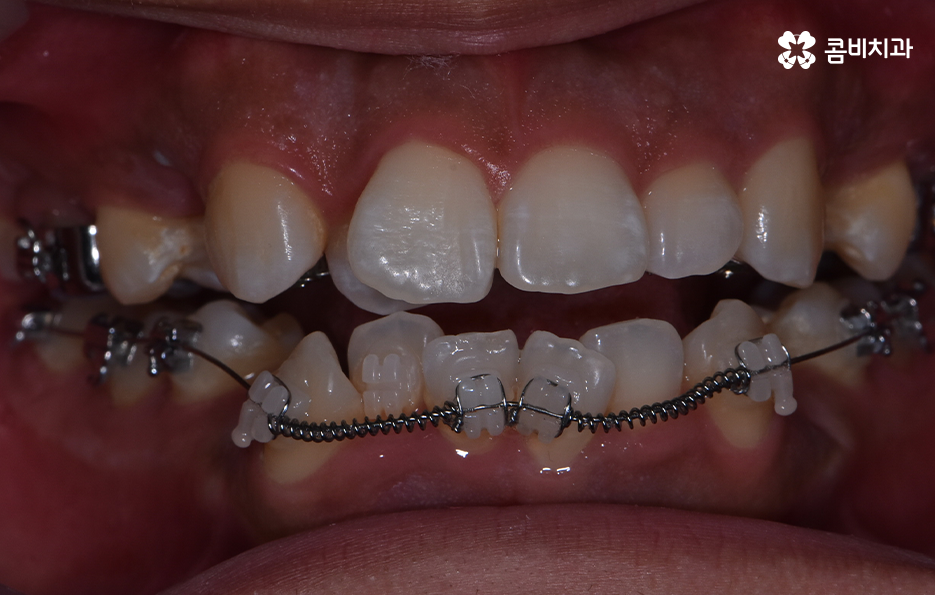

치아교정을 위한 발치교정 과정은 대부분 소구치 라고 불리는 첫번째 작은 어금니를 발치하게 되며 좌우, 위 아래 총 4개의 소구치를 발치한 후에 덧니가 재배열 될 수 있는 공간을 만들기 위하여 우선 송곳니를 후방으로 이동시키고 있어요

그 다음으로는 송곳니가 후방으로 이동하면서 확보된 공간으로 앞니의 배열을 가지런하게 맞추고 있는데요. 앞니의 재배열과 함께 발치 교정으로 인해 빈 공간이 발생한 부분을 없애고 전체적인 치열을 미세하게 조절하게 되는데 발치교정은 치아의 움직임이 많은 편이기 때문에 교합이 잘 맞도록 마무리 배열을 잘해야 하며 그와 함께 치아가 많이 움직이는 만큼 얼굴형의 변화와 입술라인 등의 변화가 클 수 있다는 점에서 치료 후 결과를 잘 예측하여 처음 치료 계획부터 마무리까지 섬세하게 진행하실 필요가 있어요